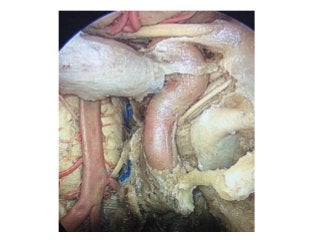

Right enlarged middle fossa approach. The internal

auditory canal has been opened, revealing the acousticofacial

Perve bundle contained within it. The facial nerve runs anteriorly,

and the superior vestibular nerve lies posteriorly. The

loop of the anterior inferior cerebellar artery runs near the

Meatus, below the acousticofacial nerve bundle.